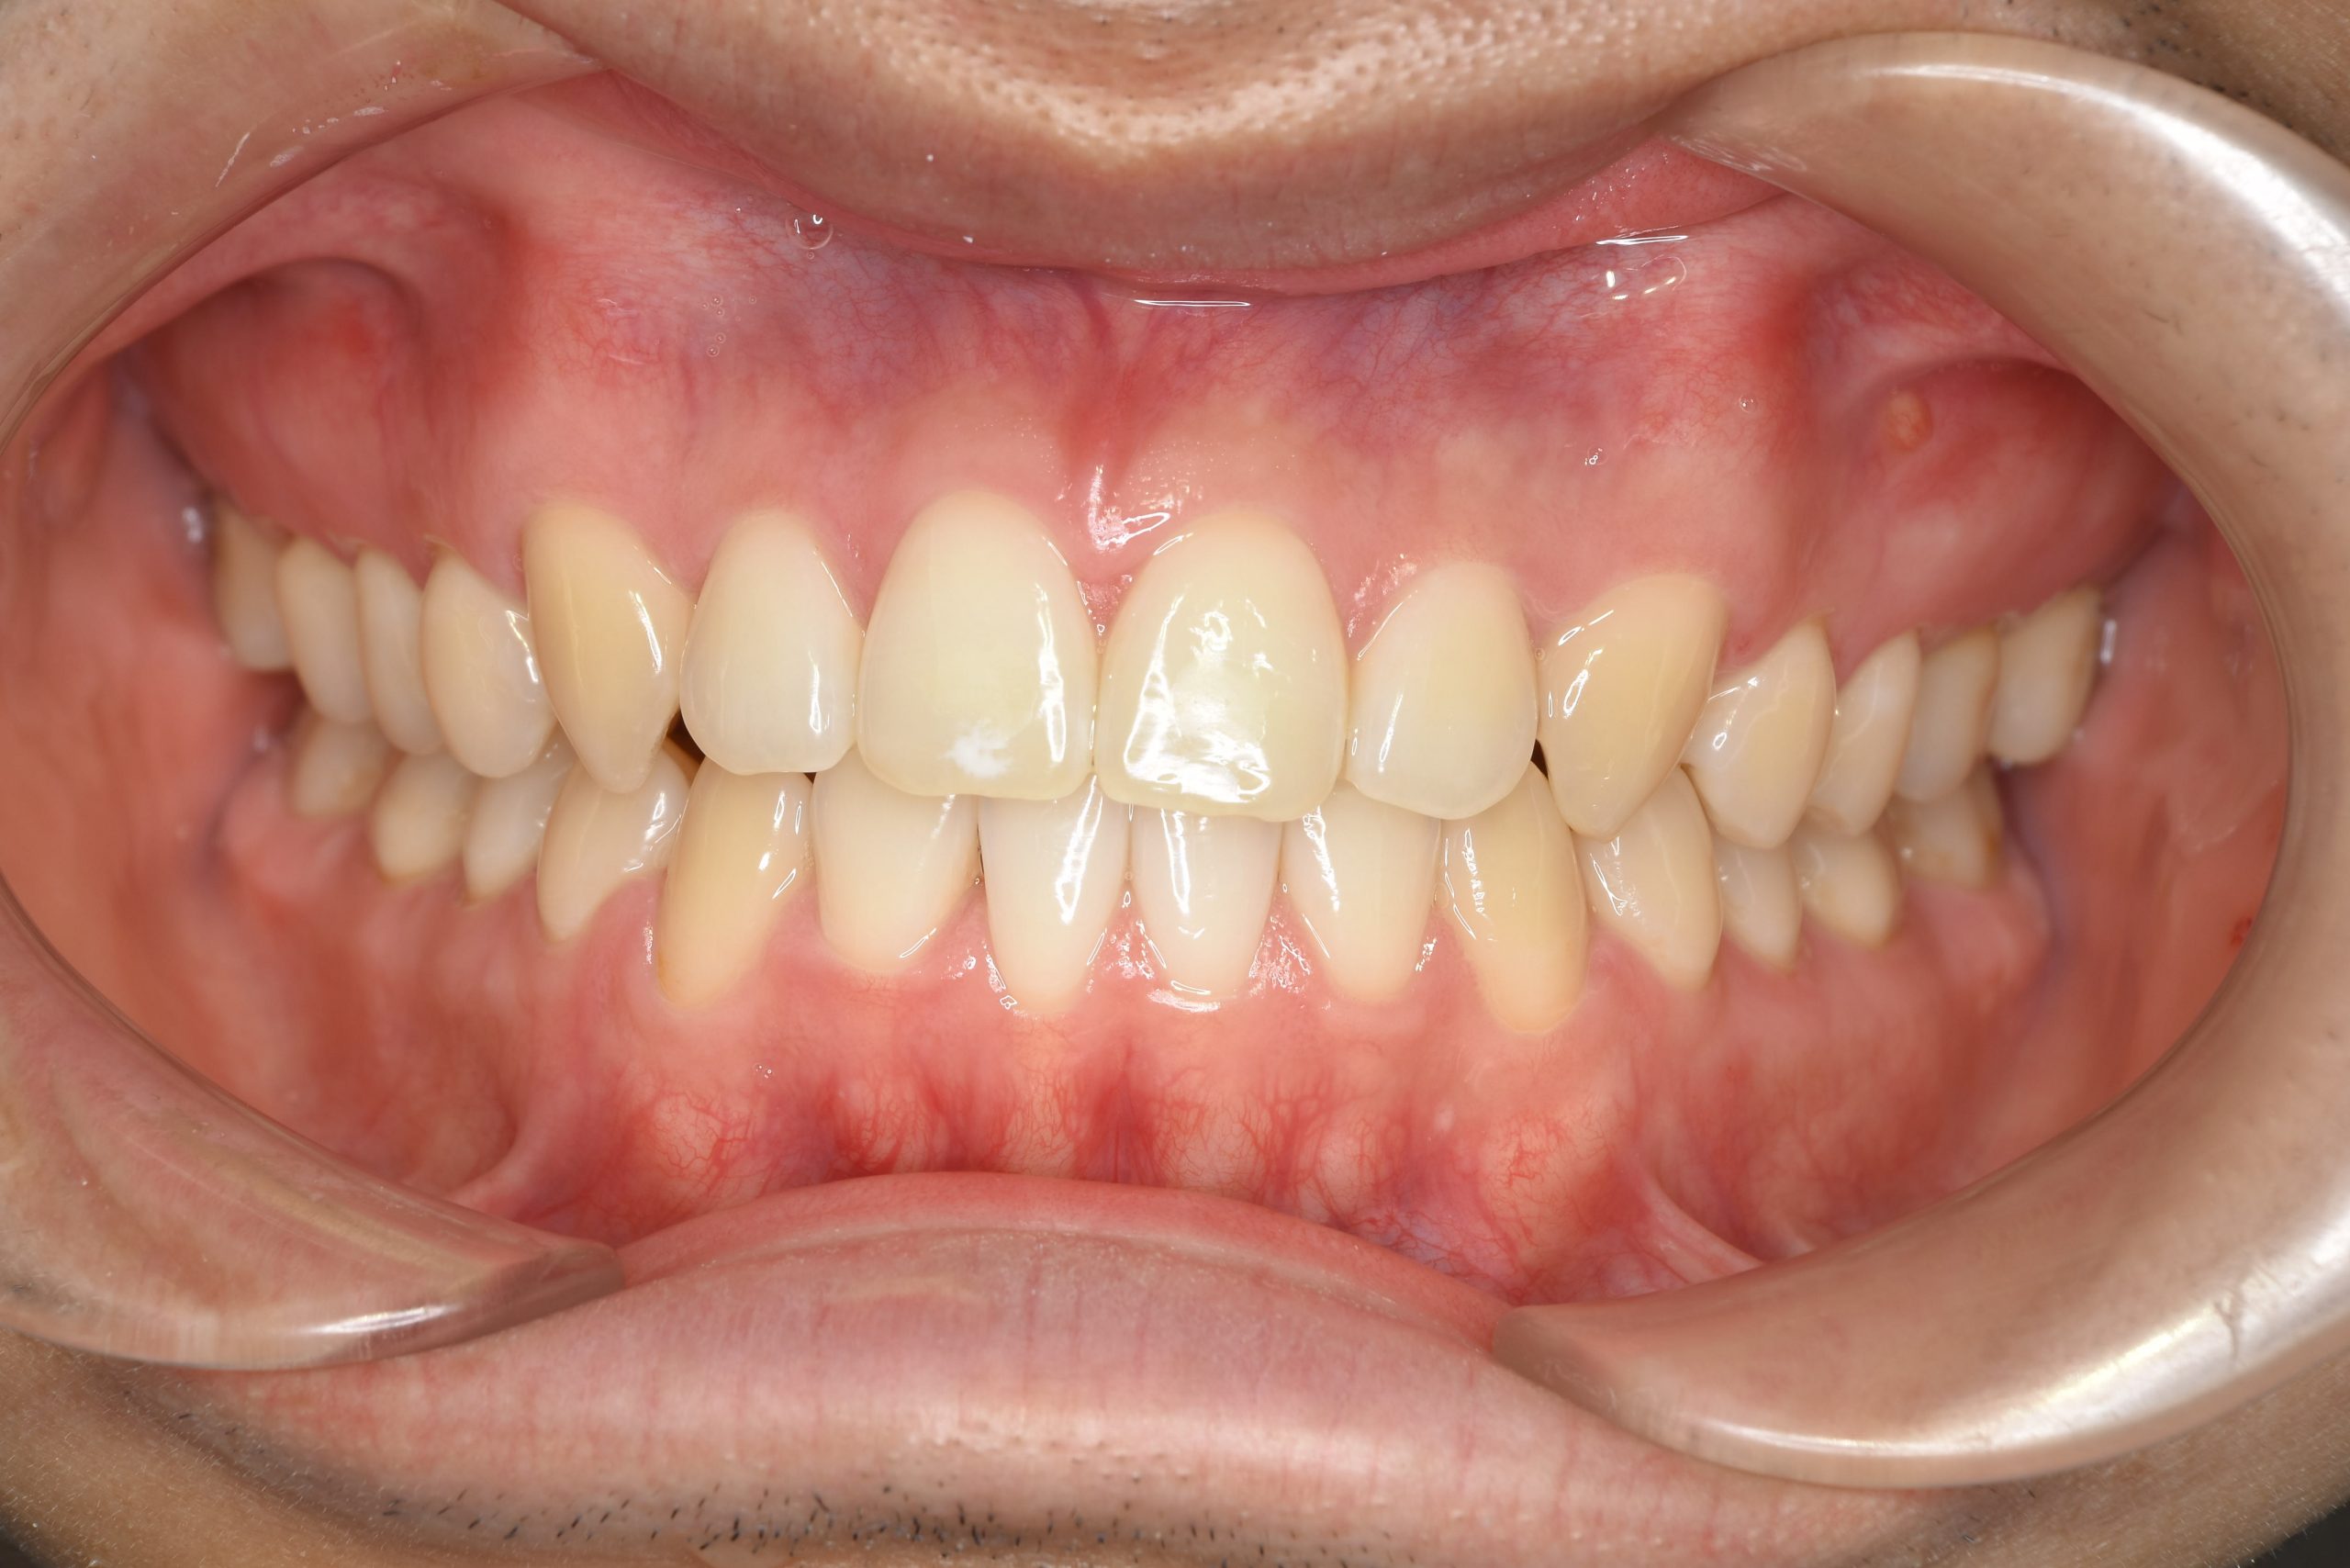

アフター

ワイヤー矯正治療|症例_495

施術内容 MSEと下顎リンガルアーチを用いて上下顎骨を拡大した。

その後マルチブラケット装置とミニインプラントを用いて

非抜歯で歯牙を配列し、良好な咬合を獲得した。

下口唇の突出感と鼻閉症状は改善した。

治癒期間 2年1か月間